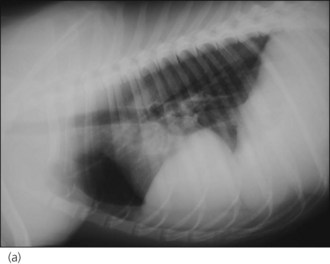

Pulmonary contusions

Pulmonary contusions represent areas of alveolar and interstitial haemorrhage and oedema, and probably represent the most common thoracic injury in dogs and cats following trauma. Not all affected animals develop associated clinical signs and pulmonary contusions may occur with or without other thoracic injuries. Clinical signs may develop acutely or over several hours, and radiographic changes may lag behind clinical signs by up to 24 hours. Radiographic abnormalities (patchy or diffuse alveolar or interstitial lung changes) may persist for a variable period of time despite clinical improvement (Figure 28.4). There is no specific treatment for pulmonary contusions and management typically involves oxygen supplementation, cage rest, analgesia as indicated for concurrent injuries, minimal stress and time.

image

Figure 28.4 Right lateral thoracic radiograph of a cat showing pulmonary contusions.